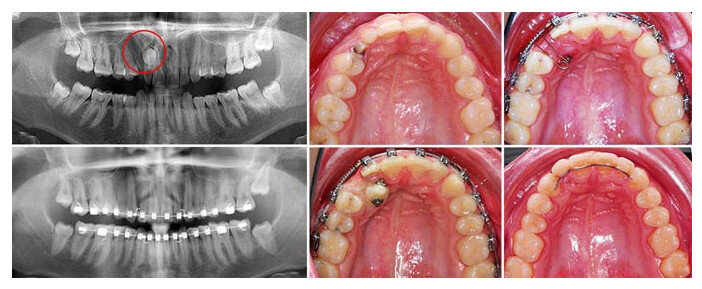

Найти полностью ретинированные зубы – это настоящий квест. Их может быть вообще не видно, потому что они расположились под существующими элементами зубного ряда. В таком случае вариант диагностики только один: необходимо делать полный снимок челюсти, на котором будет отлично видно всю картину. Ниже на картинке – подборка примеров. Ретинированные зубы отмечены красным или стрелками.

Примеры ретинированных зубов на рентгеновском снимке